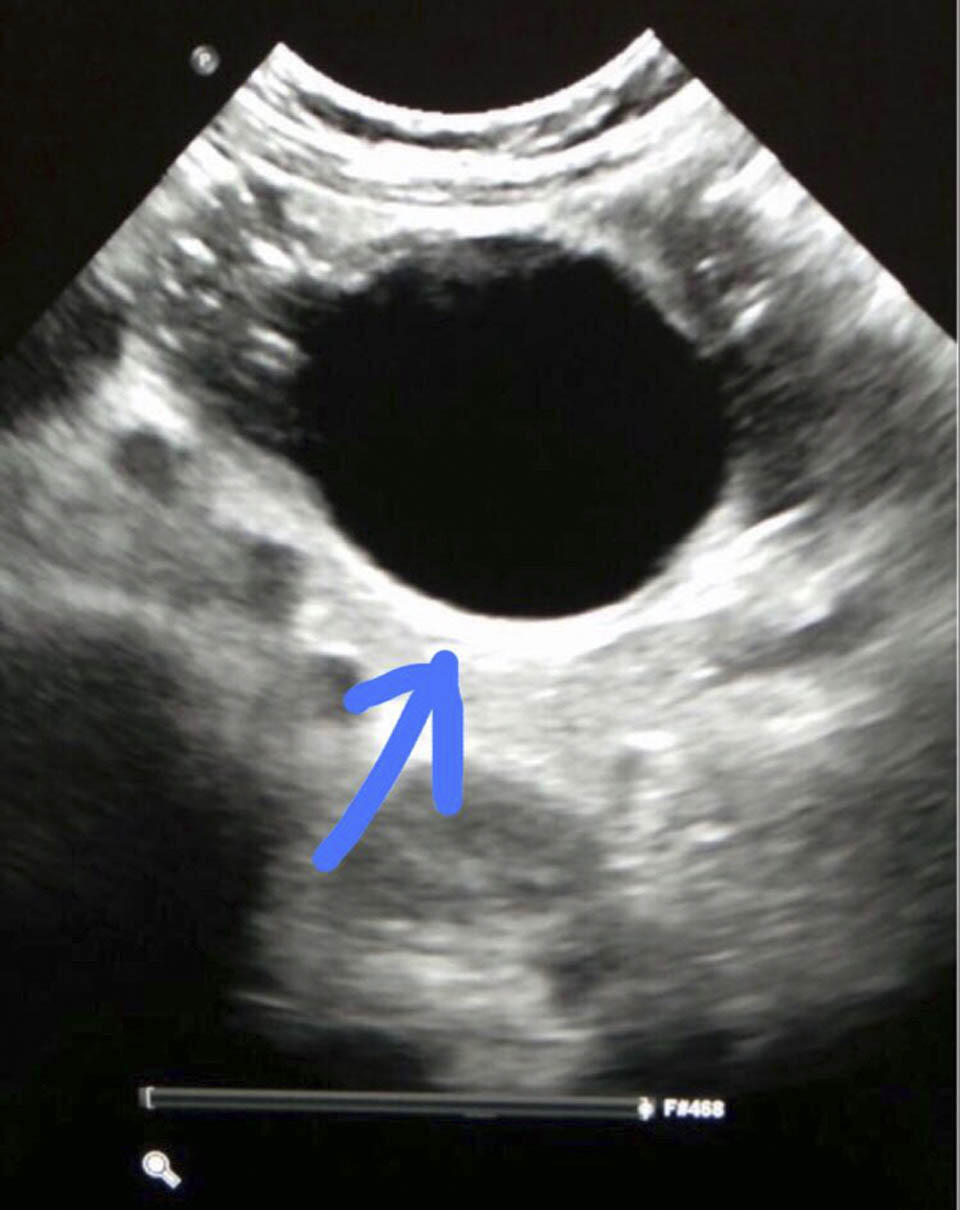

Малышу сделали УЗИ и выявили кистообразное образование, закупоривающее кишечник. Но природа этого новообразования поначалу не была ясна.

Вскоре выяснилось, что ребенок проглотил гелевый шарик, который разбух у него в кишечнике и вызвал непроходимость. С помощью щадящих хирургических методов врачи осторожно извлекли шарик и отправили ребенка в хирургическое отделение для дальнейшего наблюдения.